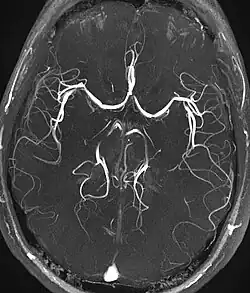

Magnetic resonance angiograph created by the ToF method

For magnetic resonance angiography (MRA), ToF is a major underlying method. In this method, blood entering the imaged area is not yet saturated, giving it a much higher signal when using short echo time and flow compensation. It can be used in the detection of aneurysm, stenosis or dissection.[5]